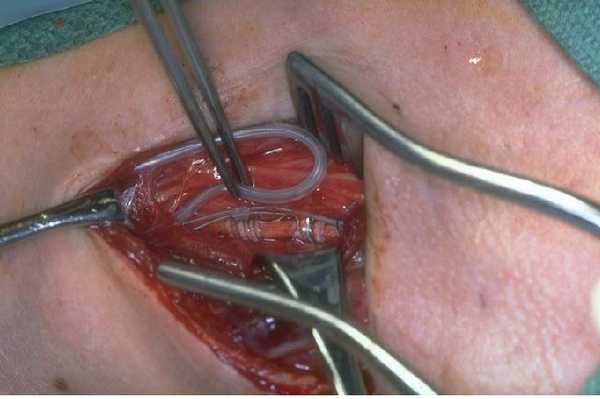

Этап 1. В области передней поверхности шеи слева делается первый небольшой разрез, проводится тупой доступ к левому блуждающему нерву, расположенному между яремной веной и сонной артерией. Затем два электрода и якорь прикрепляются к левому блуждающему нерву (рисунок 1).

Рисунок 1. Прикрепление электродов к левому блуждающему нерву.

В левой подмышечной или подключичной области делается второй разрез. Проводится туннелизация: подкожное проведение кабеля электродов от места первого разреза в области шеи (от места прикрепления электродов к блуждающему нерву) до второго разреза в области левой подмышечной/подключичной области). Электрод посредством кабеля соединяется с генератором

Этап 2. Генератор импульса устанавливается под кожей, в левой подмышечной/подключичной области (рисунок 2).